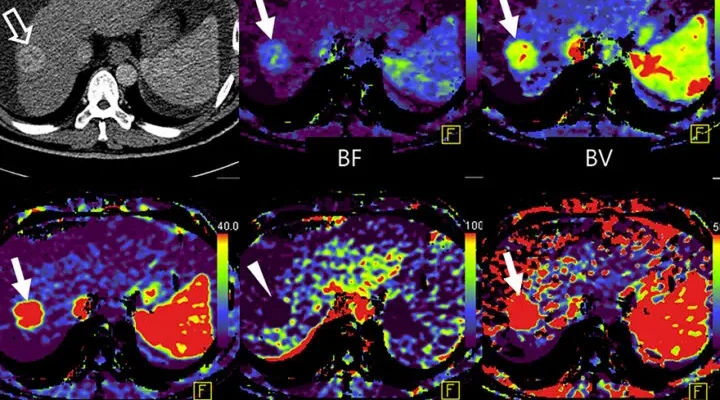

- Beyin Tümörleri: Perfüzyon MR, beyin tümörlerinin teşhisinde de kullanılır. Bu yöntem, tümörün büyüklüğünü ve tipini belirleyerek tedaviye uygunluğunu değerlendirmeye yardımcı olur.

Perfüzyon MR, inme veya beyin tümörleri gibi hastalıkların teşhisi ve tedavisinde de kullanılır. Örneğin, inme sırasında beyindeki kan akışı bölgesel olarak değişebilir ve bu değişiklikler perfüzyon MR ile görülebilir. Benzer şekilde, tümörlerin çevresindeki damarların yapıları ve işlevleri, perfüzyon MR ile değerlendirilebilir.